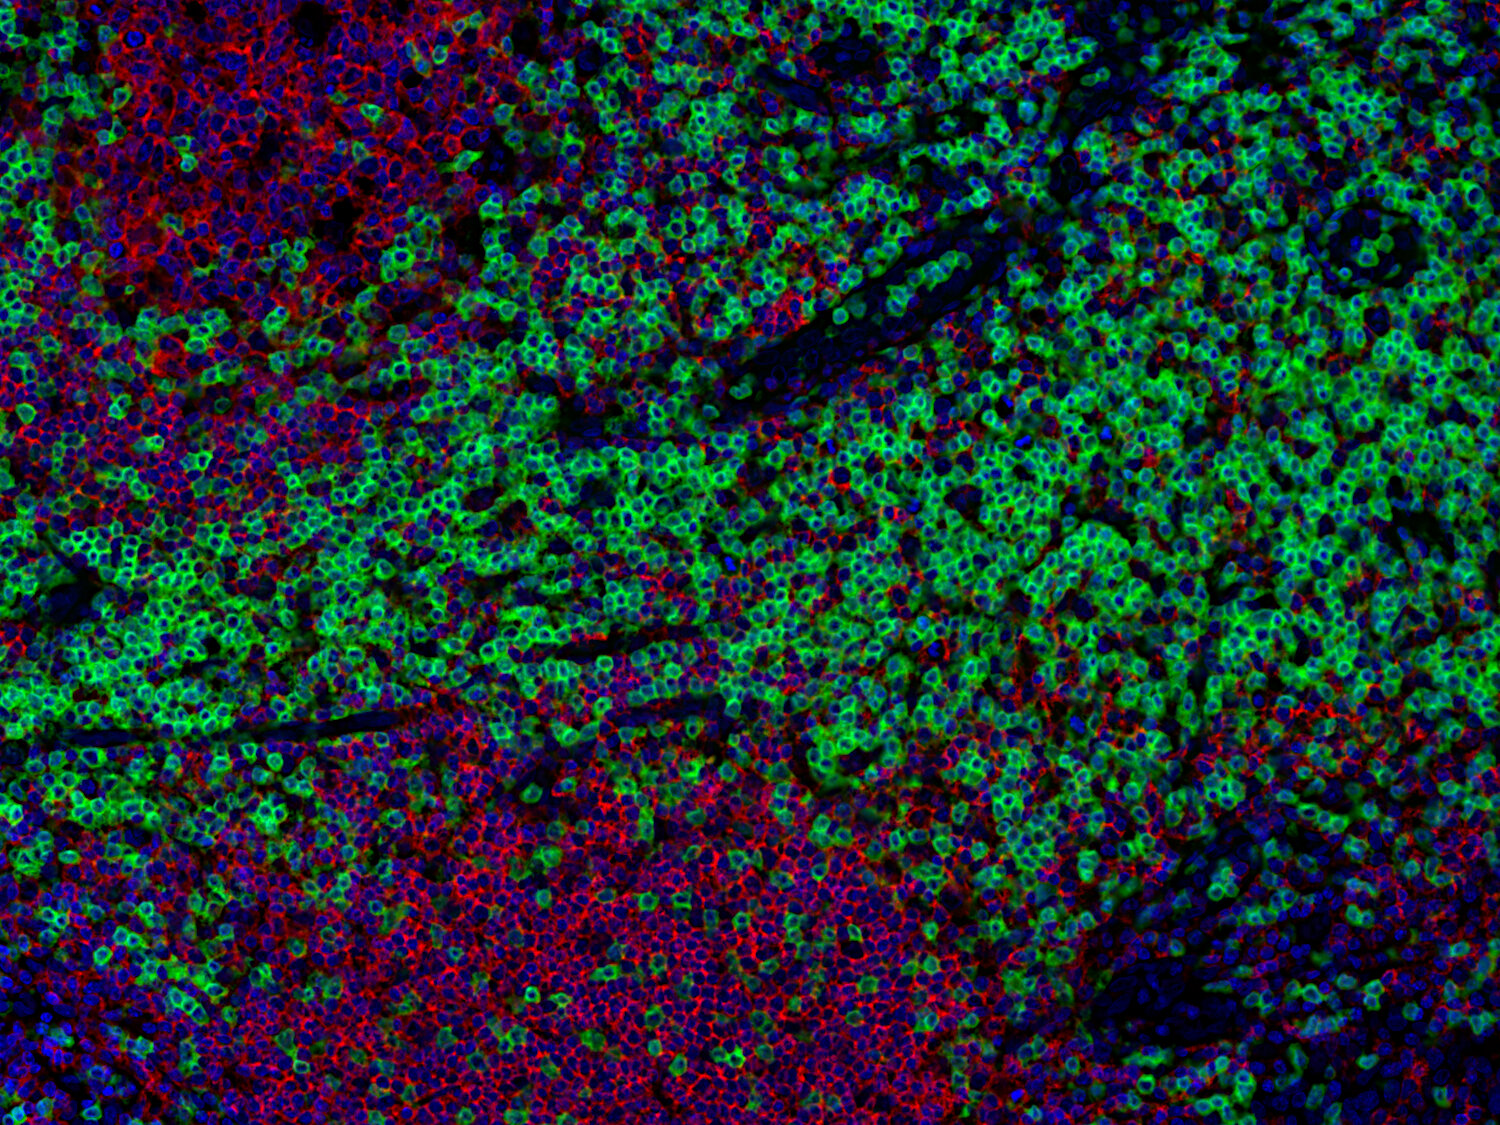

IHC-P: 1 : 1000 up to 1 : 4000 gallery

Immunohistochemistry (IHC-P) of formalin fixed, paraffin embedded (FFPE) tissue (some antibodies require special antigen retrieval steps, please refer to the ”Remarks” section). Immunoreactivity is usually revealed by fluorescence or a chromogenic substrate.

This product belongs to the HistoSure product line of antibodies developed for and extensively tested in FFPE tissues.

Cluster of differentiation 3 (CD3) is a defining feature of cells belonging to the T cell lineage. It is composed of the four subunits CD3 gamma, CD3 delta, CD3 epsilon (CD3e) and CD3 zeta, that form a multimeric protein complex. This complex associates with the T cell receptor (TCR) and serves as a T cell co-receptor. The CD3 molecules contain immunoreceptor tyrosine-based activation motifs (ITAMs) that serve as the nucleating point for the intracellular signal transduction machinery upon TCR engagement. TCR/CD3 signaling is central to the initiation of antigen-specific T cell responses to pathogens and vaccines, as well as transplanted tissues, tumors, and autoantigens. CD3 is initially expressed in the cytoplasm of pro-thymocytes. During T cell maturation the expression of CD3 migrates to the cell-membrane. The specific appearance at all stages of T cell development make CD3 a useful immunohistochemical marker for T cells in tissue sections. In the clinical setting, CD3 is a relevant marker for the classification of malignant lymphomas and leukemias as the antigen remains present in almost all T-cell lymphomas and leukemias. It can also be used to detect T cells in celiac disease, lymphocytic and collagenous colitis.